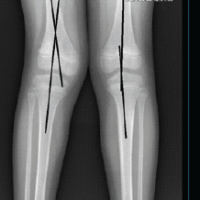

DEXA scan revealed no evidence of osteoporosis, and the patient underwent an oncological workup to rule out any metastatic cause for the pathological fracture. The patient subsequently underwent right cemented THR using the lateral approach. A cyst-like lesion was identified in the right femoral neck, which was excised and sent for histopathological examination. The patient’s post-operative radiograph was satisfactory (Fig. 3), and the patient was ambulated on the 1st post-operative day with support. The staples were removed after 2 weeks.

Figure 3: Post-operative radiograph showing cemented total hip replacement (right hip).